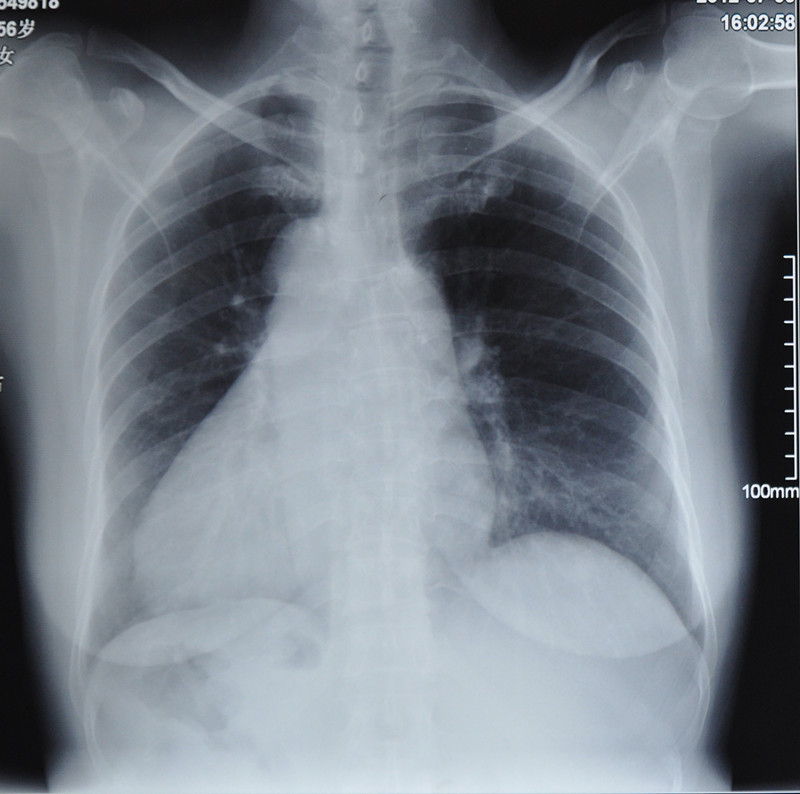

• 亚心医院成功为“镜面人”装双腔心脏起搏器

近日,武汉亚洲心脏病医院收治的一名女性心脏病患者令医生“大开眼界”,患者的内脏位置竟然跟正常人完全相反,心脏居然位于右胸,极为罕见。据悉这就是全内脏反位的“镜面人”,人群中仅为十万分之一,而为“…

2012-07-20 查看详情>